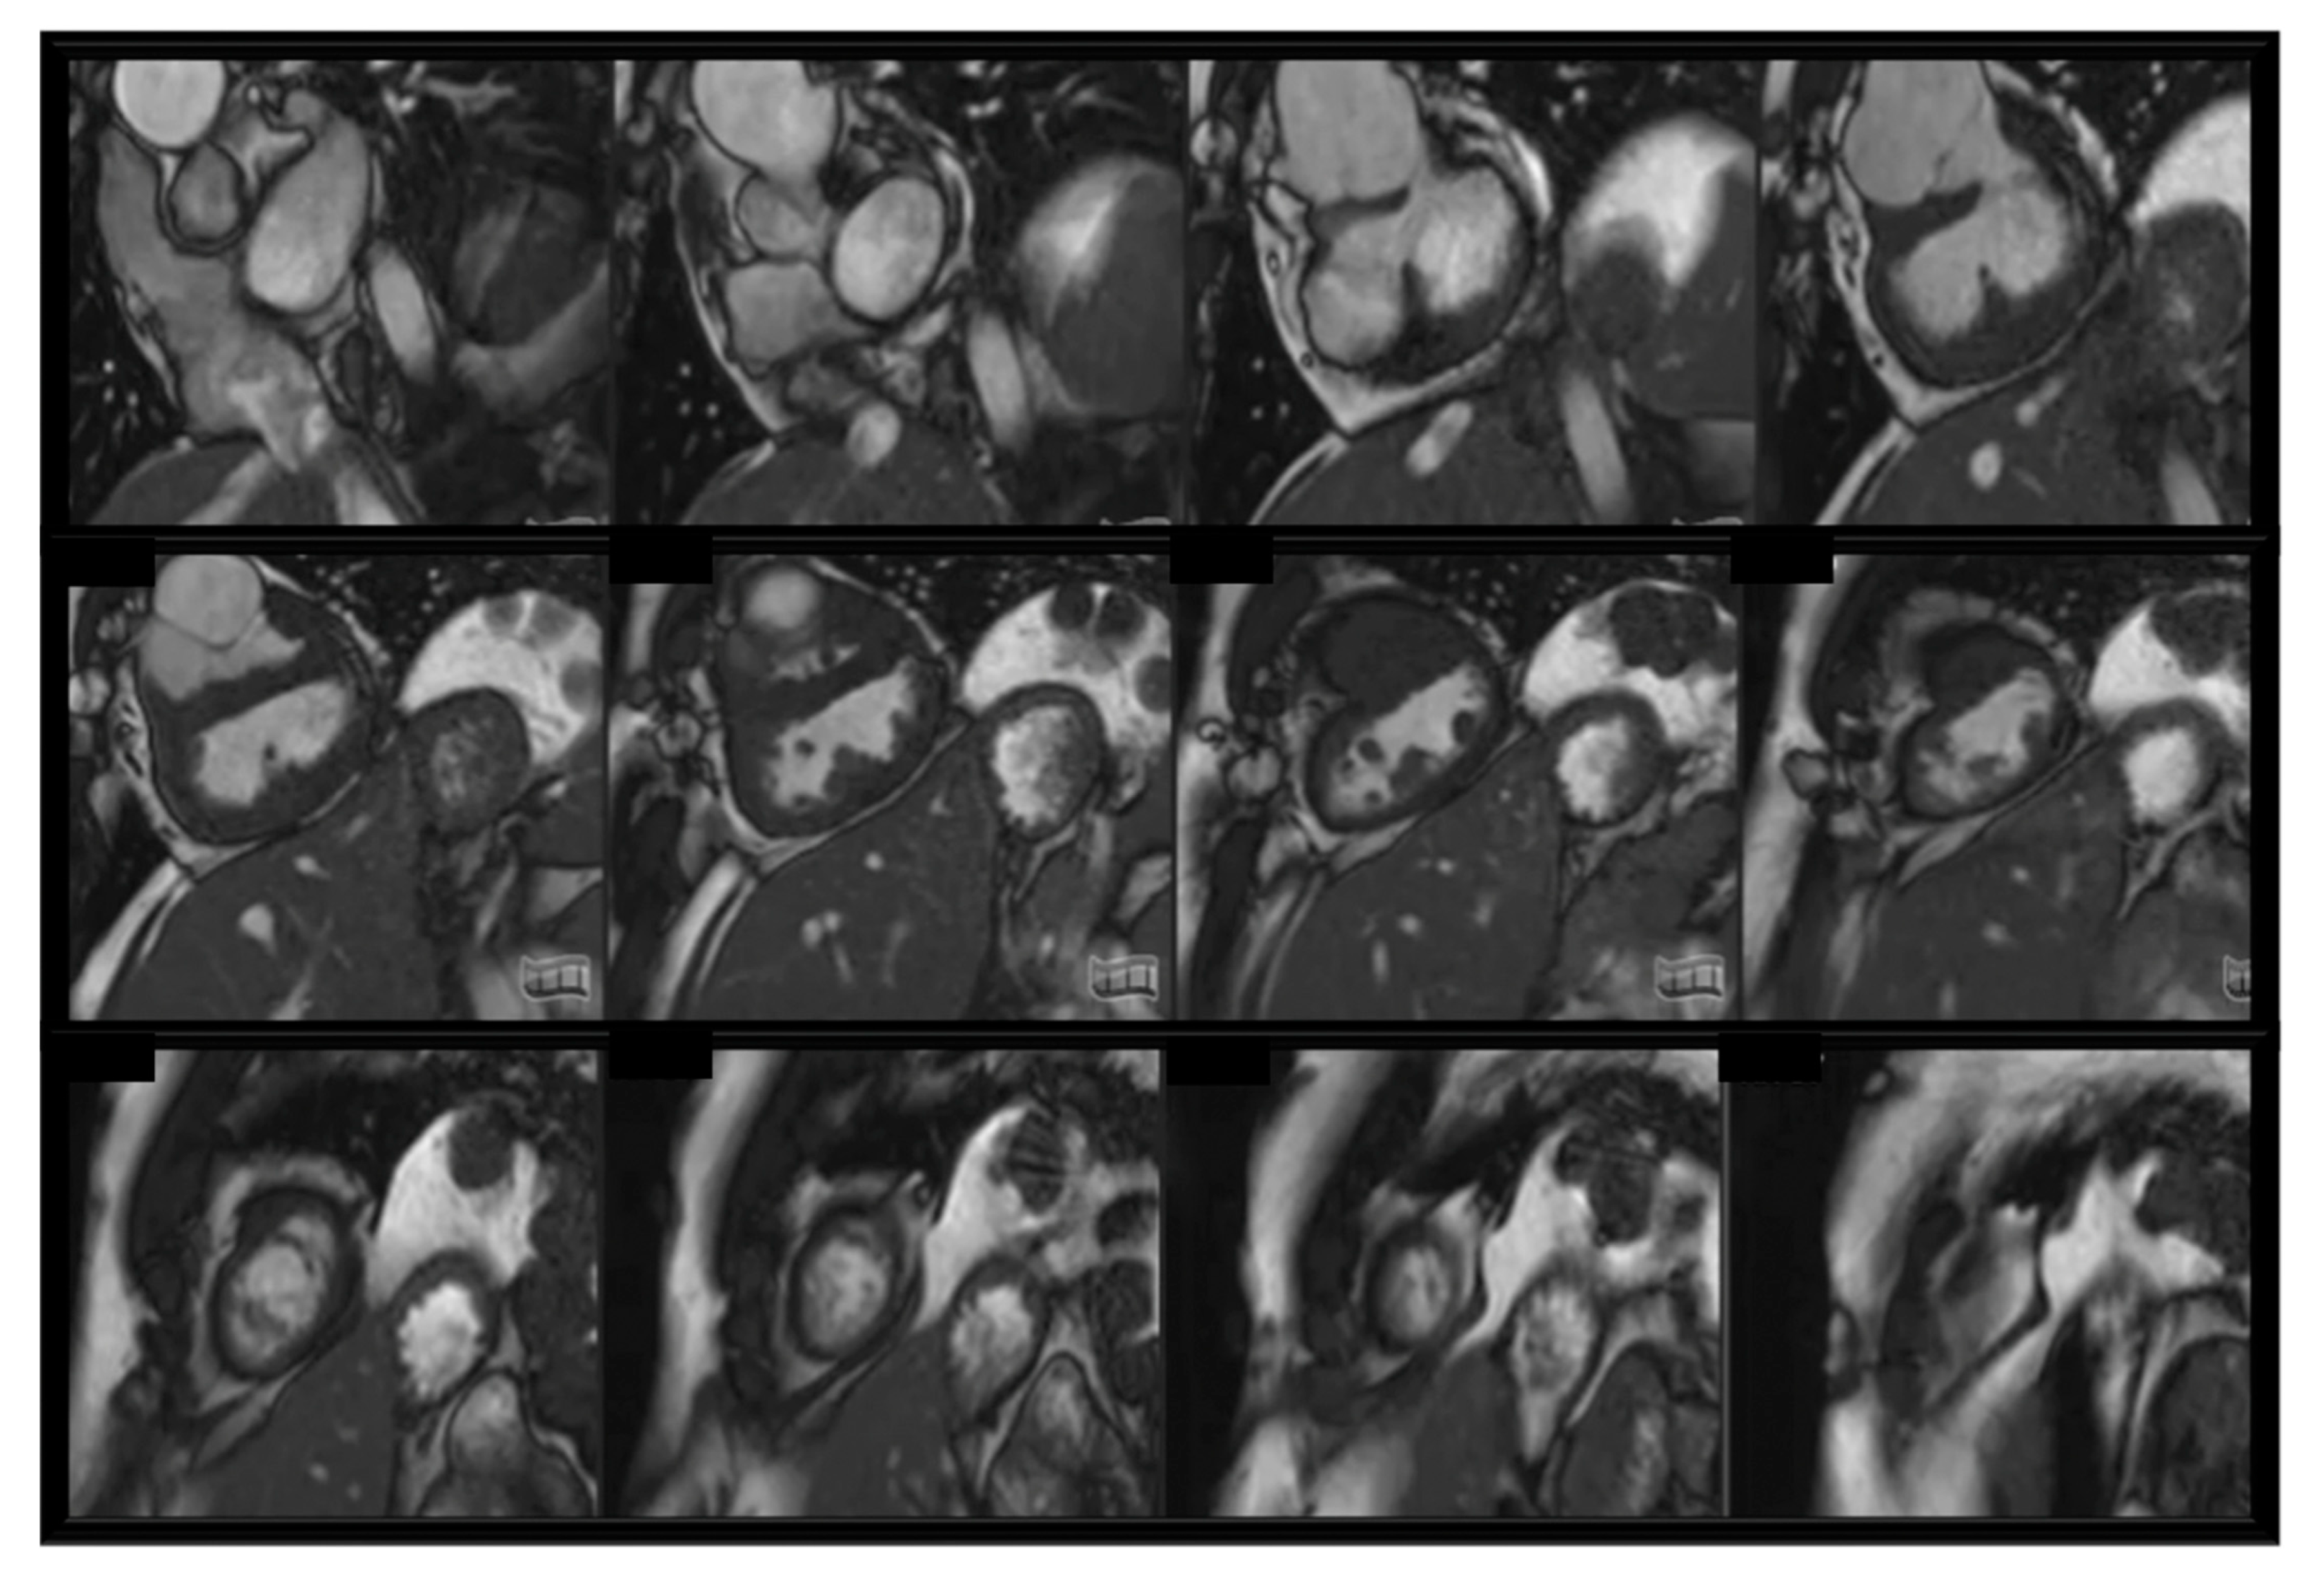

- Steady-state free precession sequences (SSFP): blood appears bright. Two-dimensional (2D) SSFP is the most frequent sequence to assess anatomy, function, and valve motion in CHDs. SSFP cine slices stuck are usually used to assess ventricular volumes and ejection fraction. Cardiac motion controlled by retrospective ECG-gating. Recommended for: baseline heart assessment and CHDs including single ventricles [48]; see Figure 1.

- Single ventricles: CMR provides detailed anatomical, functional and flow assessment throughout palliative stages in single ventricle setting as well as during follow up after completion of the Fontan circulation (Fontan pathway obstruction, baffle leaks, lung flow distribution, thrombus formation and collateral flow) [63]; see Figure 2;